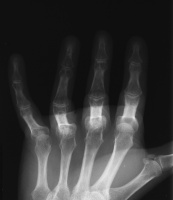

Lateral view shows PIP joint space narrowing, more pronounced in the ring finger. They also show periarticular osteoporosis of the middle and ring fingers compared to  the index and small - impressive in that this is four years post injury and the patient uses the fingers normally within the constraints imposed by contractures.